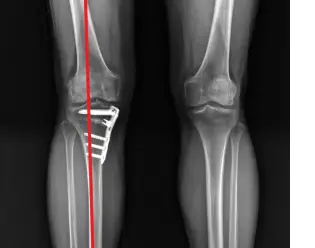

고정술: 금속판과 나사를 사용하여 골절된 뼈를 고정하는 방법입니다.

절골술: 골절된 뼈의 일부를 절단하고 제거하거나 삽입한 다음 나머지 뼈를 고정하는 방법입니다.

무릎 관절염으로 인한 심한 통증과 변형이 있는 경우, 근위경골절골술이 적합할 수 있습니다. 병원에 가면 의사는 검사, X-ray 및 MRI를 통해 뼈의 상태를 평가하고 수술이 적합한지 여부를 결정하게 됩니다.

근위경골절골술 후 회복 과정

수술 후 회복 시간은 개인의 건강 상태와 수술의 유형에 따라 다릅니다. 일반적으로 완전히 회복하는 데 몇 개월이 걸립니다. 이 기간 동안 다음 지침을 따르는 것이 중요합니다. 수술하고 처음 하게 되는 재활 치료가 위에 사진에 보이는 기구로 하는 치료입니다. 본인이 가능한 가동 범위부터 점차 각도를 늘려서 무릎을 굽혀 주는 재활 치료 기구입니다.

※ 저의 경우 2달 후 땅을 밟을 수 있었고, 목발은 5개월간 짚고, 운동 능력과 통증, 가동 범위는 작년 9월 말에 수술하고 9개월을 지나고 있는 현재 90% 회복이 된 거 같습니다.